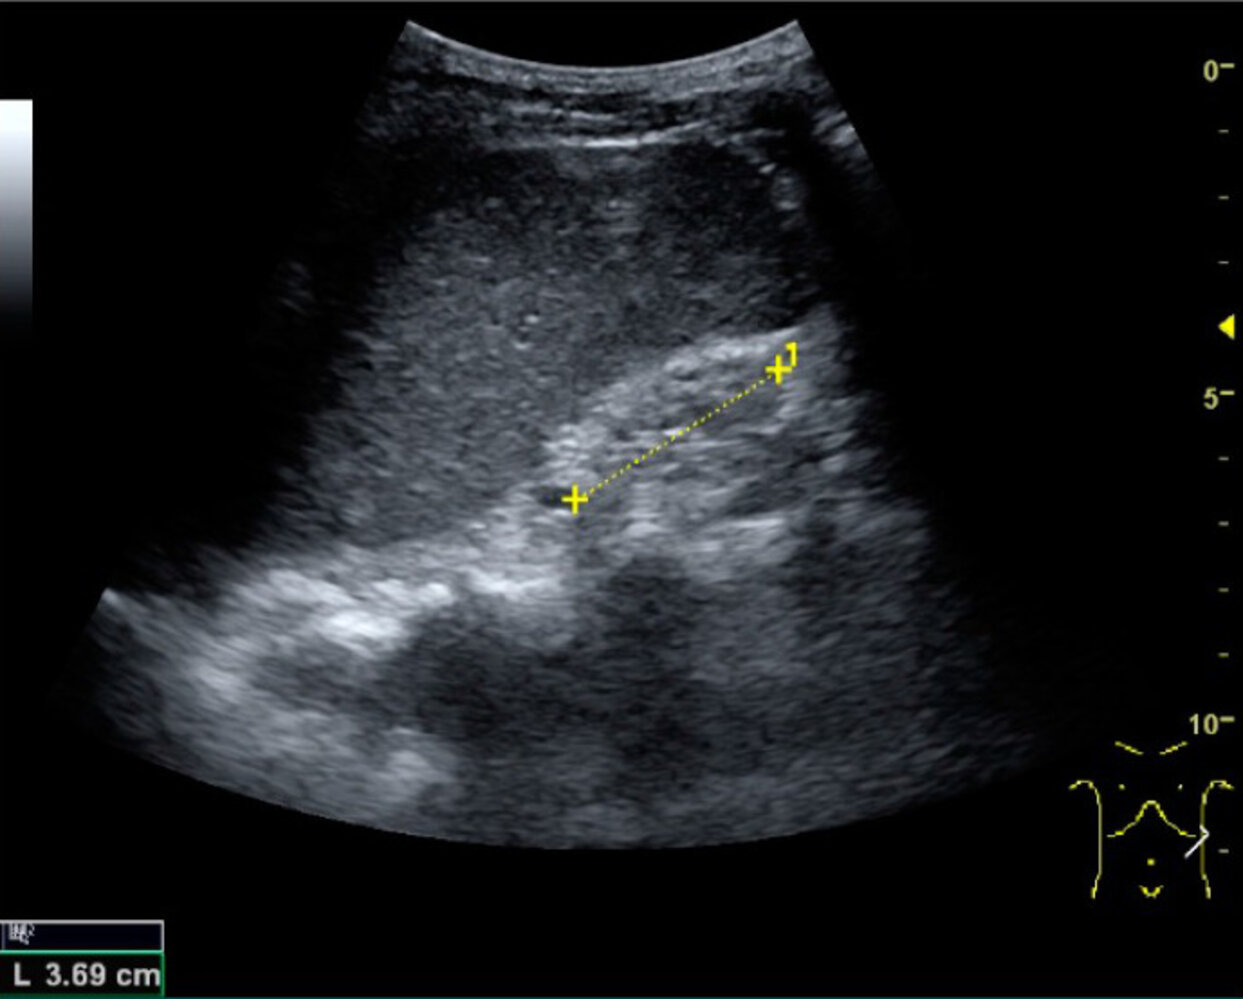

Ultrasound of the kidneys and urinary tract [8]

• First-line imaging technique for the assessment of kidney structure

• Consider obtaining for all patients to further support the diagnosis and help determine the etiology.

• Findings that suggest chronic kidney damage include: [14]

• Kidney length (< 10 cm)

• ↓ Parenchymal and/or cortical thickness

• ↑ Cortical echogenicity

• Cysts

• Calcifications

• Findings that suggest specific etiologies

• Ureteral or renal pelvic dilation suggests obstructive nephropathy.

• Bilaterally enlarged kidneys with multiple cysts suggest polycystic kidney disease.

• Cortical nephrocalcinosis suggests chronic glomerulonephritis or chronic pyelonephritis. [15]

Consider obtaining an ultrasound of the kidneys and urinary tract as part of the routine evaluation of all patients with CKD.